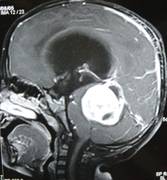

Publications on the subject : M.R.I. in A.R.M.